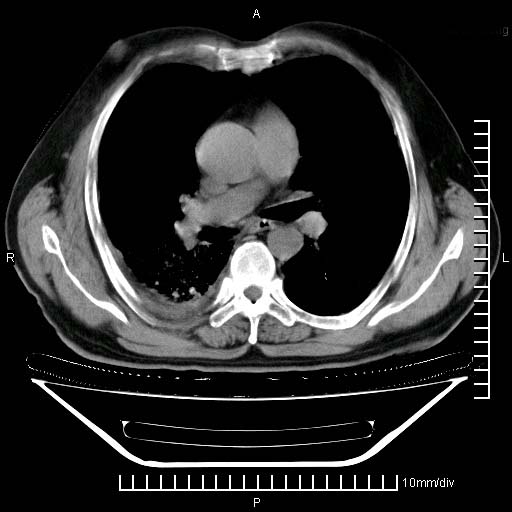

既往肺结核,近10几天,咳嗽,咳痰,右侧胸痛,疼痛较明显,右上肺斑块考虑结核灶胸膜粘连,增强,可惜动脉期没有定好,未见强化,可延迟4分后又见较明显强化,中心见低密度影,如果说结核是边缘强化,可这个灶强化的面积挺大的,让人很挠头。

强化的组织可能是膨胀不全的肺组织或炎性肉芽组织。

1)两肺继发性肺结核。2)右侧胸膜增厚+少量胸腔积液。